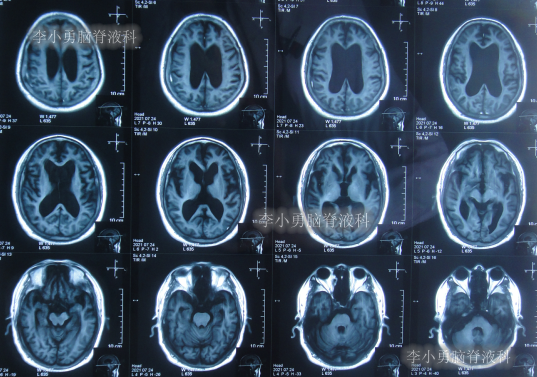

2020年10月29日(发病已8年),因症状一直没有得到改善且呈进行性加重趋势,查头部核磁示脑积水(图-1)。

图-1:2020年10月29日头部核磁